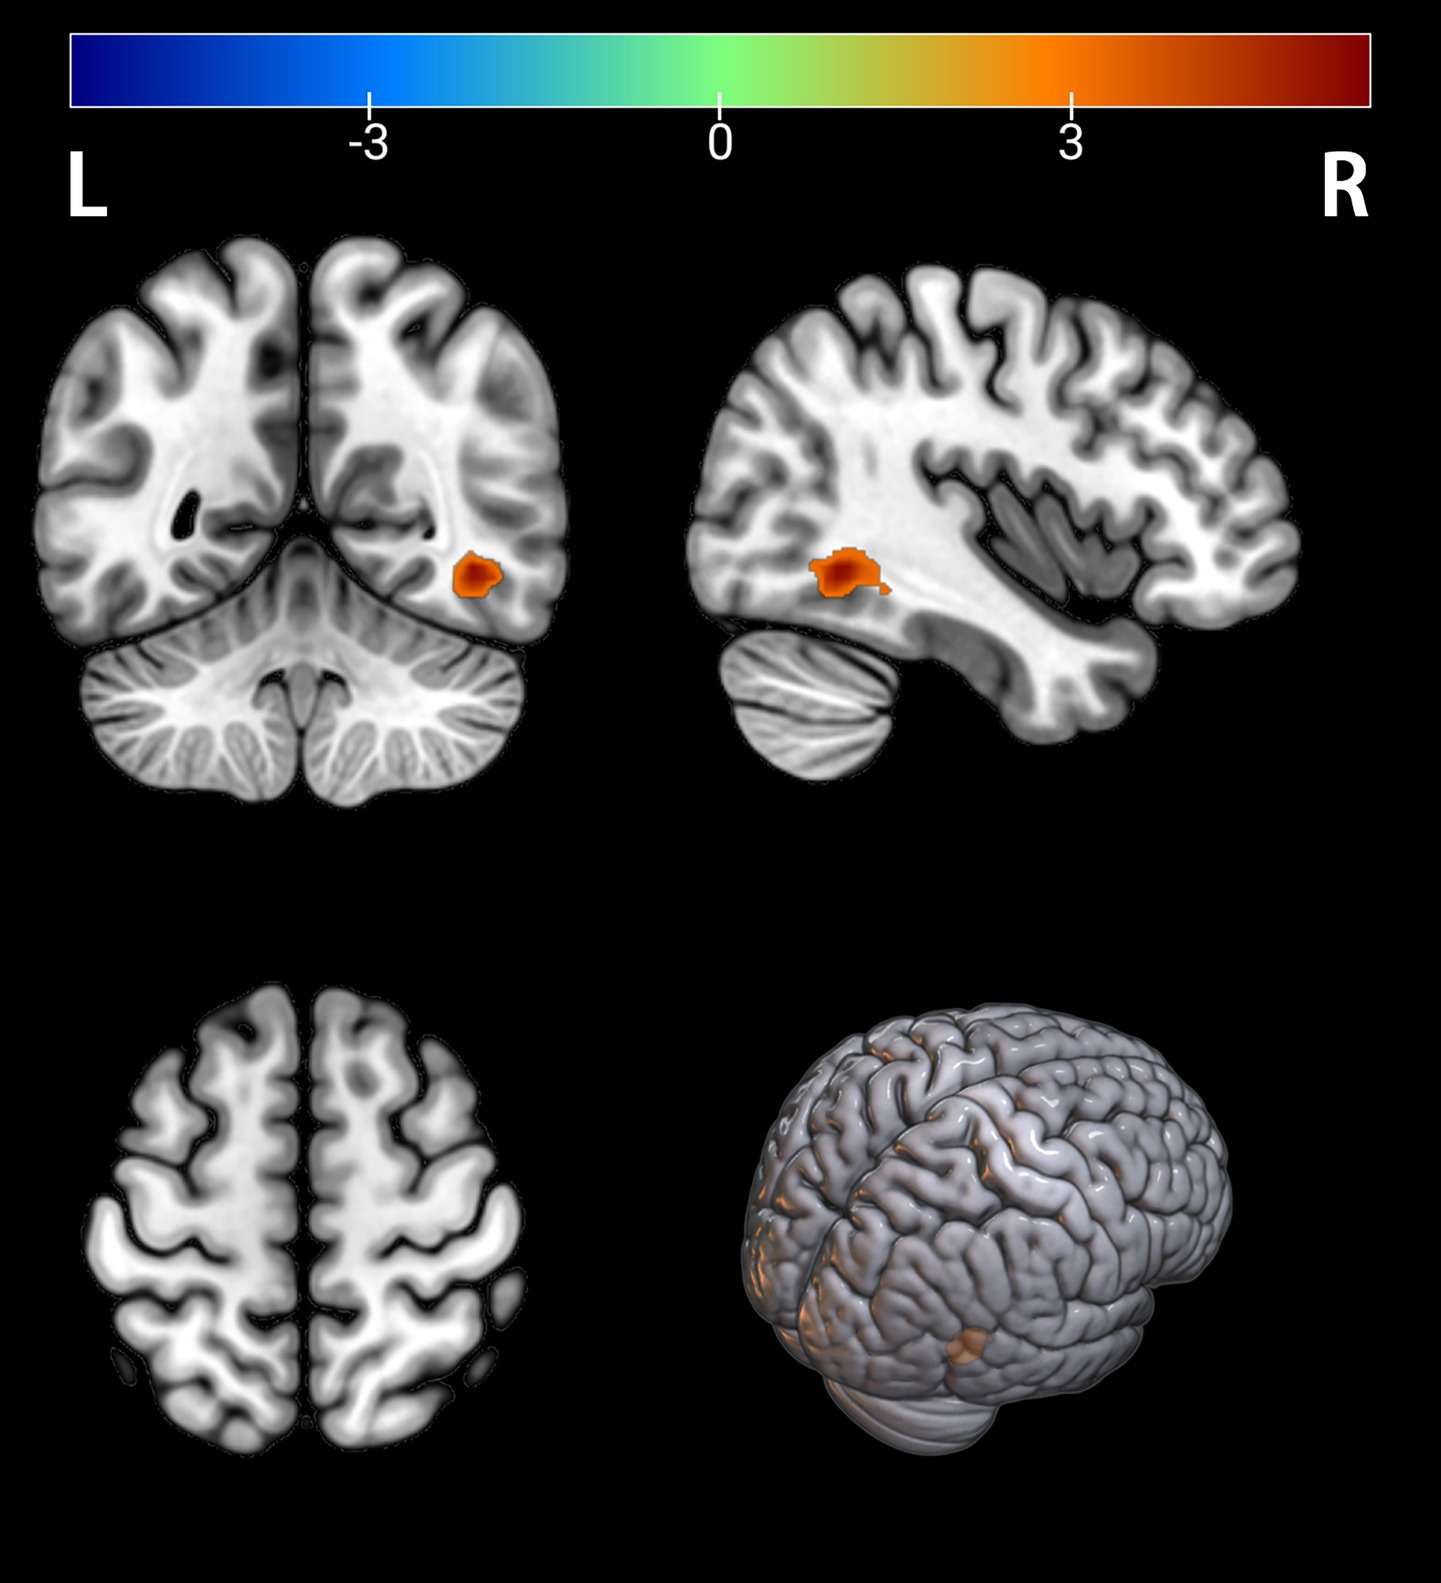

Figure 5

Brain regions with significant differences in functional connectivity within the VIN between the PT and HC groups. The results are displayed on a 3D brain template. Statistical significance was determined by a two-sample t-test (FWE-corrected at the cluster level with a voxel-wise initial threshold of p < 0.001). The color bar represents the T-value. Warm colors (red) indicate a significant increase in functional connectivity in the PT group. The peak of the significant cluster is located in the right inferior temporal gyrus (Temporal_Inf_R). R, right; L, left.

Figure 6

Brain regions with significant differences in functional connectivity within the visual network (VIN) between the PT and HC groups. The results are displayed on 2D axial slices for detailed anatomical localization. Statistical significance was determined by a two-sample t-test (FWE-corrected at the cluster level with a voxel-wise initial threshold of p < 0.001). The color bar represents the T-value. Warm colors (red) indicate a significant increase in functional connectivity in the PT group. The peak of the significant cluster is located in the right inferior temporal gyrus (Temporal_Inf_R). R, right; L, left.

3.4 ICA analysis of differences

There were differences in connectivity within the visual network (VIN) between the two groups, with the peak point of difference being in the Temporal_Inf_R brain region (Table 4), and elevated connectivity in the depressed group in the Temporal_Inf_R brain region (FWE-corrected, voxel p < 0.001, cluster p < 0.05, Figures 5, 6).

Table 4

| Temporal_Inf_R (aal) | 42 | −51 | −6 | 5.5899 | 44 |